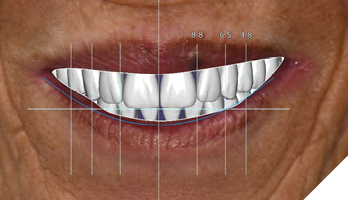

The data recorded during the clinical exam in conjunction with the FMS xrays and CT scan data were analyzed, and a diagnosis was made as to the viability of the patient’s existing teeth. A virtual diagnostic wax up was completed using prosthetic planning software (ExoCad) (Figs. 4A, 4B). The .STL file of the virtual wax up was integrated with the CT scan data in implant surgical planning software (3Shape Implant Studio) and a surgical plan was designed (Figs. 5A, 5B). The viability of this surgical plan was then evaluated in conjunction with the previously determined prognosis of the patient’s existing dentition and surrounding periodontium, and a treatment plan was formulated. The plan with the anticipated predictability of achieving the planned result was presented to the patient. The patient approved the treatment plan.

Fig. 4A

Fig. 4B